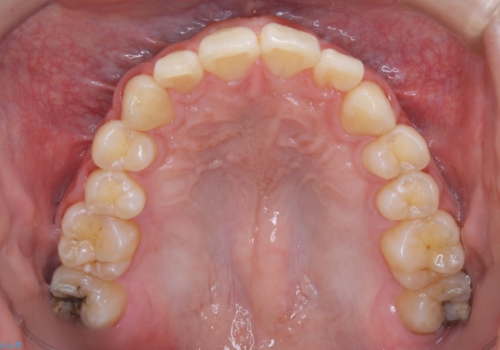

人生で初めてのクリーニングということもあり、プラークや歯石が大量に付いていました。それにより、歯茎の腫れもあり出血も多かったです。これから矯正をスタートしていくため、歯ブラシ指導を行いホームケアを頑張ってもらっています。